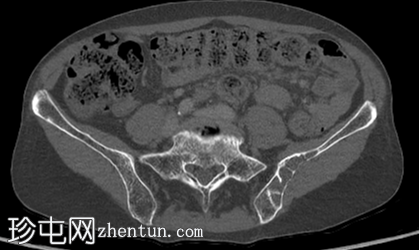

轴位增强扫描(门静脉期)

左侧髂骨内边界清晰的病灶

薄层硬化环

皮质变薄

轻微骨膨胀

内部密度低于肌肉和少量脂肪

薄骨间隔

无骨外软组织肿块